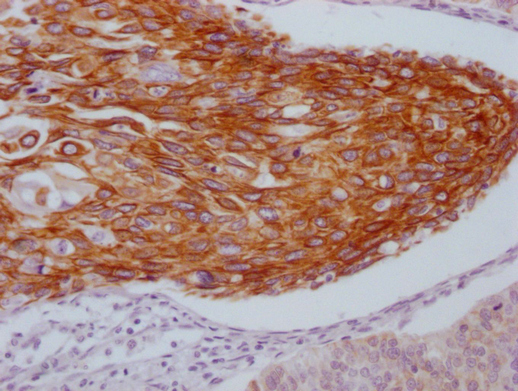

IHC image of CSB-MA550667 diluted at 1:100 and staining in paraffin-embedded human cervical cancer performed on a Leica BondTM system. After dewaxing and hydration, antigen retrieval was mediated by high pressure in a citrate buffer (pH 6.0). Section was blocked with 10% normal goat serum 30min at RT. Then primary antibody (1% BSA) was incubated at 4°C overnight. The primary is detected by a Goat anti-mouse IgG polymer labeled by HRP and visualized using 0.05% DAB.